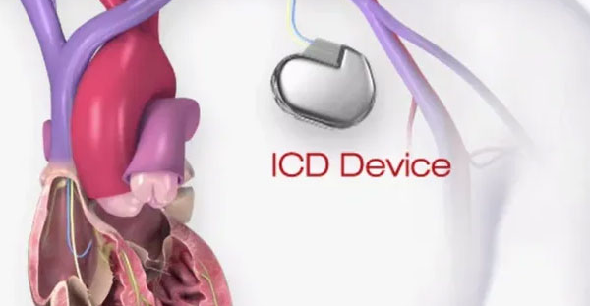

The S-ICD provides effective defibrillation for ventricular

tachyarrhythmias , significantly reduces the risk of vascular

injury at the time of implant, has a low risk of systemic infection

given no hardware in the venous system, preserves venous access

(a high priority for some patients including those with end-stage

renal disease who are on or are preparing for hemodialysis), avoids

risks associated with endovascular lead extraction if future lead

fracture or infection, and again requires no fluoroscopy at the time of implant.

Your electrophysiologist will able to discuss this option more in-depth with you

to determine if you are a good candidate and proceed with in-office required preoperative 3-lead

surface electrocardiogram screening to ensure that you are a reasonable candidate

for this therapy (given the appropriateness of surface signals).